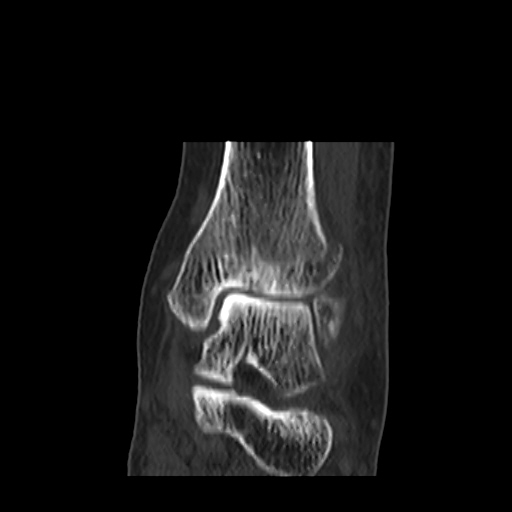

CT : avulsion fracture of distal tibia at distal tibiofibulat ligament insertion.